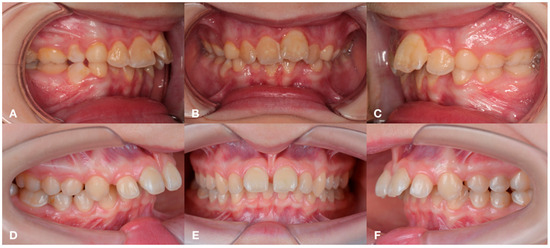

2.1. Subjects

3.1. Periodontal Status and Inflammatory Indices

3.2. Radiological Bone Density of the Jaws, Hounsfield Index Analysis